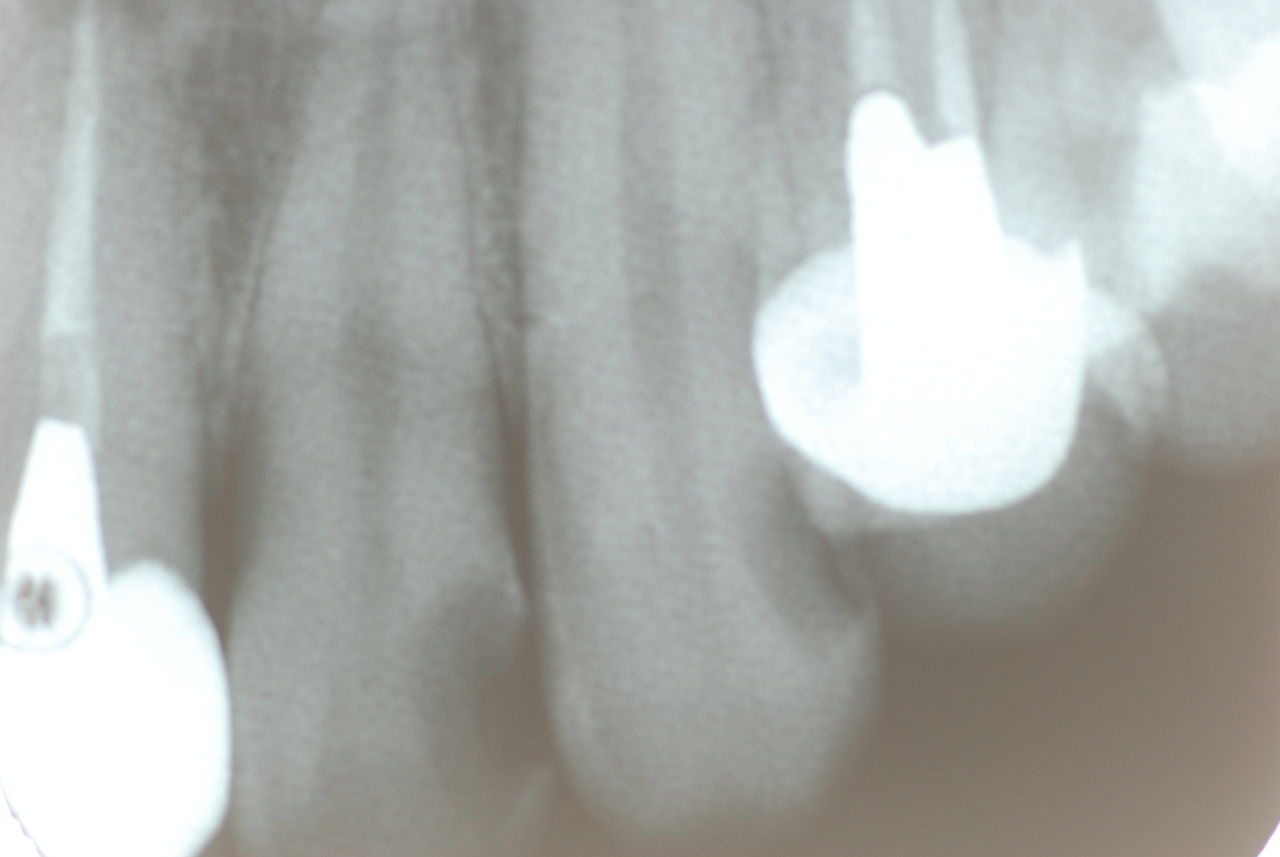

入れ歯の話から入りました。色々不満で注文があるようです。でも話が一段落して口腔内を調べると殆どの歯が重症で抜けそうな歯だらけなのです。

なぜ病気になるのかわからない方が多すぎます。歯が抜けるのは病気だからです。病気を治さずに何かお口の中に入れても土台である歯が抜けてしまっては同じことなのです。

何故歯が悪くなるのか、歯周病で抜けるのか分からなければ何を入れても歯は悪くなり抜けていくのです。